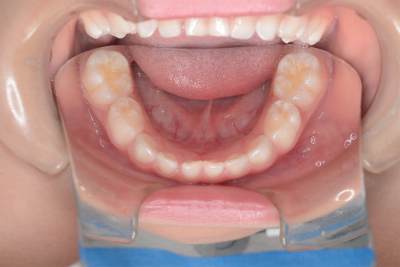

小学3年生

定期的に私の歯科医院に来てもらいフッ素を塗って歯の写真をとっていますが、今回も3人の歯にはムシ歯はありませんでした。